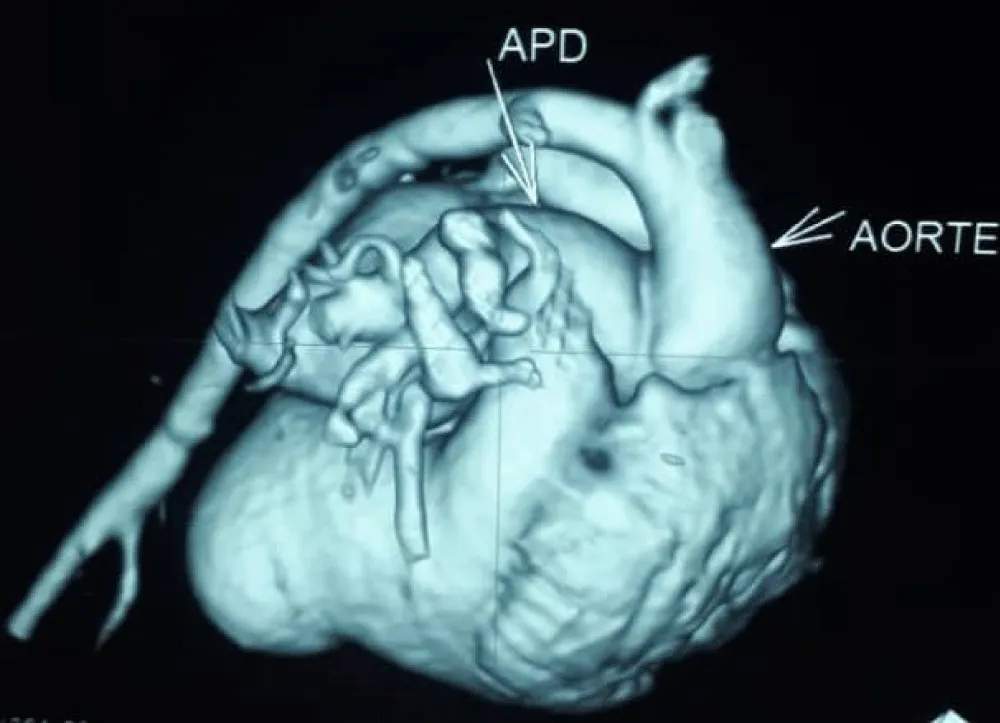

The electrocardiogram showed bi-atrial and left ventricular hypertrophy. On frontal telethorax, cardiomegaly with a supra-diaphragmatic peak, a right inferior arch overhang, and peri-hilar vascular overload, predominantly on the right. Cardiac ultrasound revealed a situs solitus heart with levocardia. The aorta normally emerges from the left ventricle, without obstruction. After a few centimeters, it gave way to a right pulmonary artery that filled correctly in systole without obstruction (Figures 1,2). The left pulmonary artery arises directly from the right ventricle. All cardiac cavities are dilated—suprasystemic pulmonary hypertension with ostium secundum-type atrial septal defect with right-to-left shunt. Cardiac angioscan confirmed the diagnosis, showing a 13 mm right pulmonary artery arising from the aorta. The left pulmonary artery arises directly from the right ventricle and measures 9.73 mm, with a functional pulmonary valve (Figures 3,4). Biological tests revealed microcytic hypochromic anemia at 9.3 g/dl. Medical treatment was based on furosemide, captopril, and spironolactone. A surgical cure after catheterization with reimplantation of the right pulmonary artery was indicated. The child died before surgery.

Figure 3: Right pulmonary artery arising from the aorta on cardiac angioscan./p>

Figure 4: Cardiac angioscan reconstruction image showing right pulmonary artery exiting the aorta.